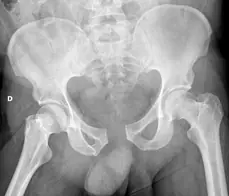

Luxation de hanche